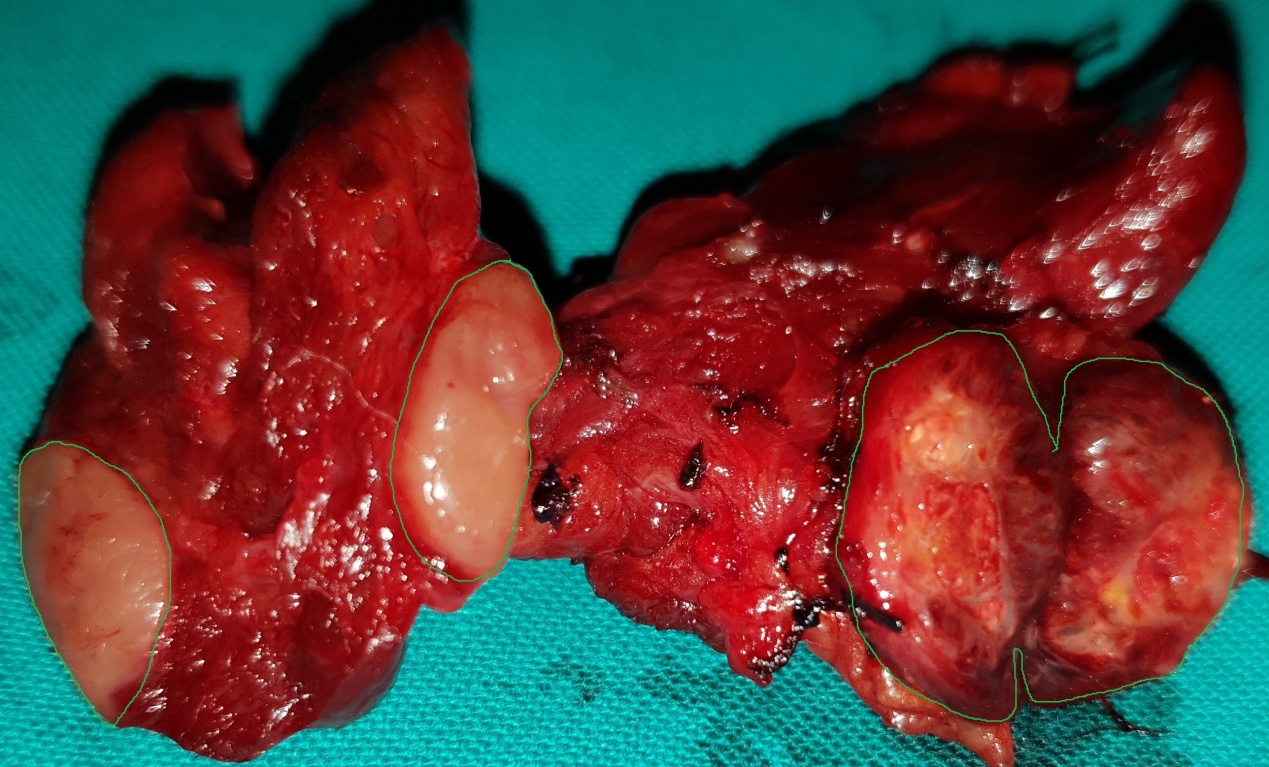

Figure 5 . Surgical specimen a) Blue arrows: encapsulated medullary microcarcinoma b) Yellow arrows : parathyroid glands . c) Green arrow : Benign thyroid nodule . ( Courtesy Dr . V . Penopoulos ) .